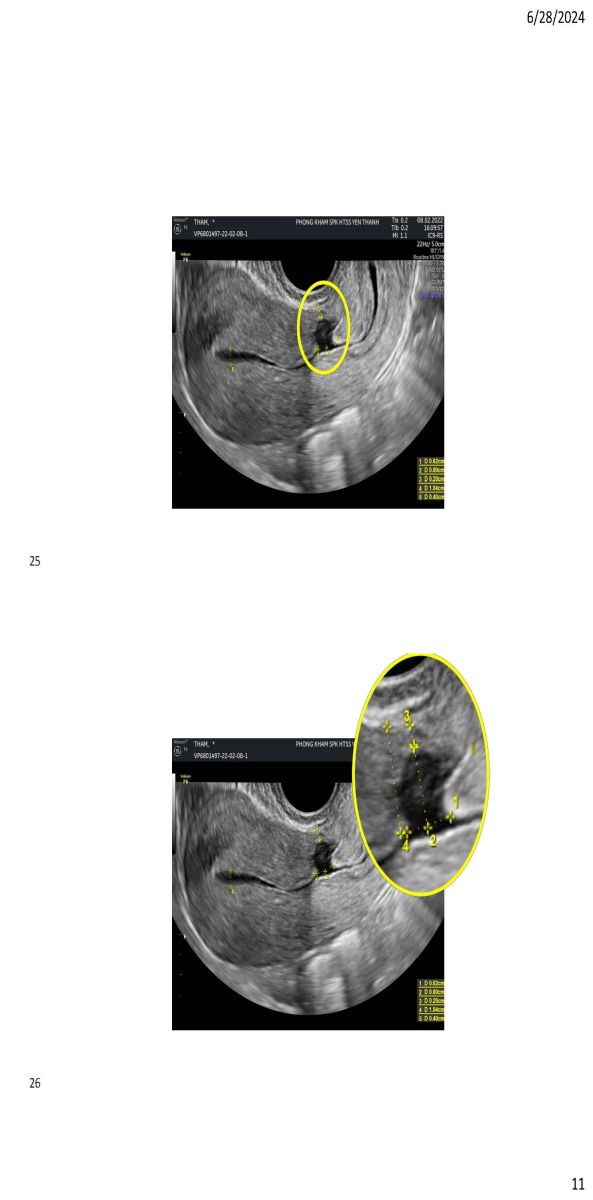

Ứng dụng siêu âm trong quyết định phương pháp can thiệp khuyết sẹo mổ lấy thai